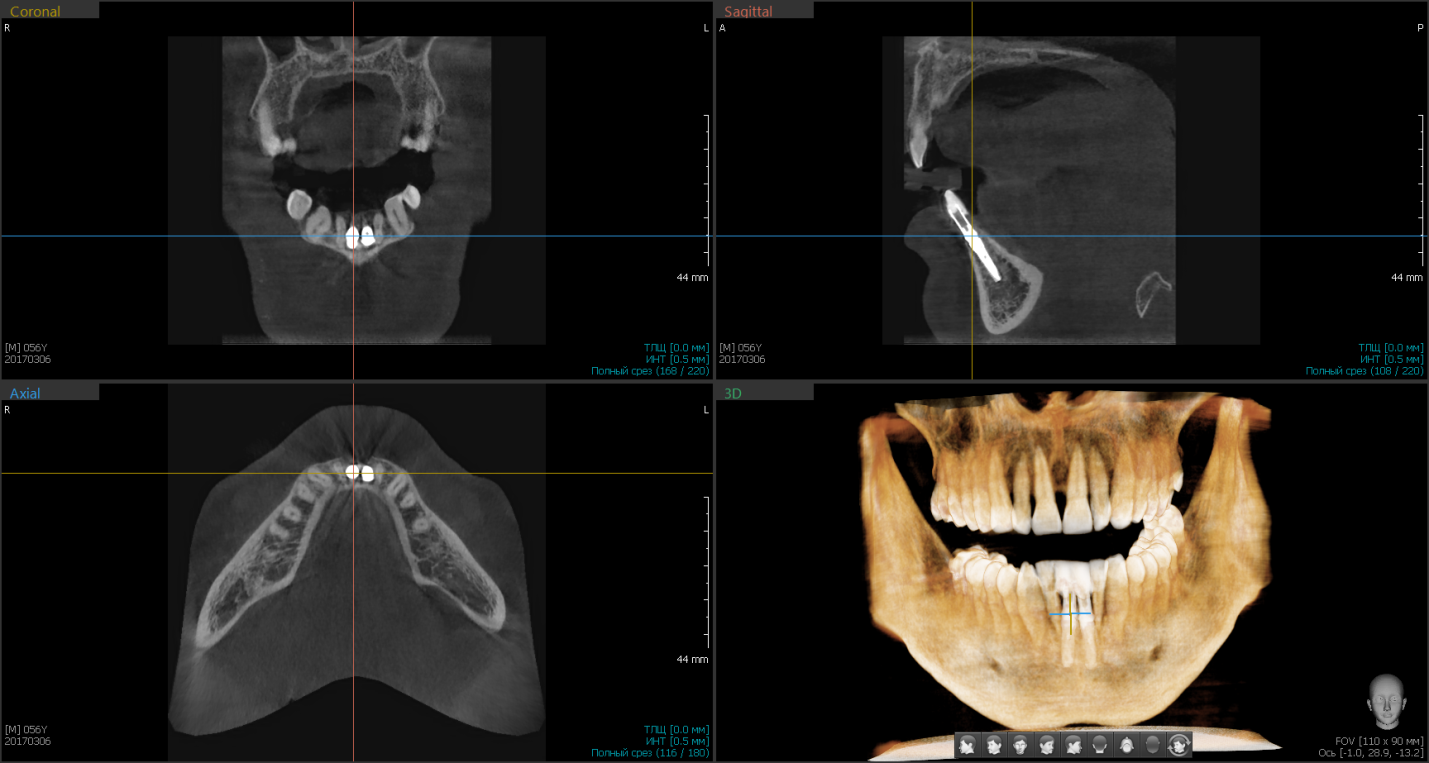

Рис. 3 Дентальная объемная томограмма после проведения одномоментной имплантации в проекции 12,22 зубов. Дефект костной ткани в области вестибулярной стенки апикальной части дентального имплантата 1.2